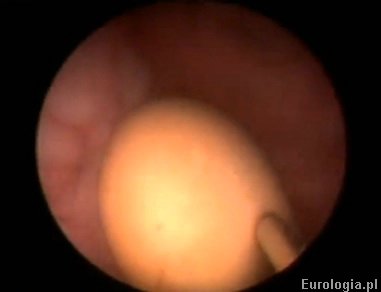

Fot. Widok kamienia w pęcherzu moczowym podczas zabiegu endoskopowego usunięcia.

Fot. Widok kamienia w pęcherzu z widoczną końcówką lithoclastu - operacja usunięcia złogu.